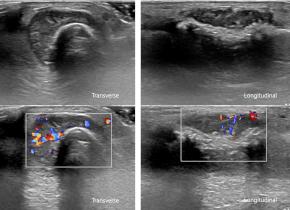

[Musculoskeletal [MS]] 83 Years/F, 2nd finger mass since 3 months ago, colon cancer history(+)

| Answer | Metastasis |